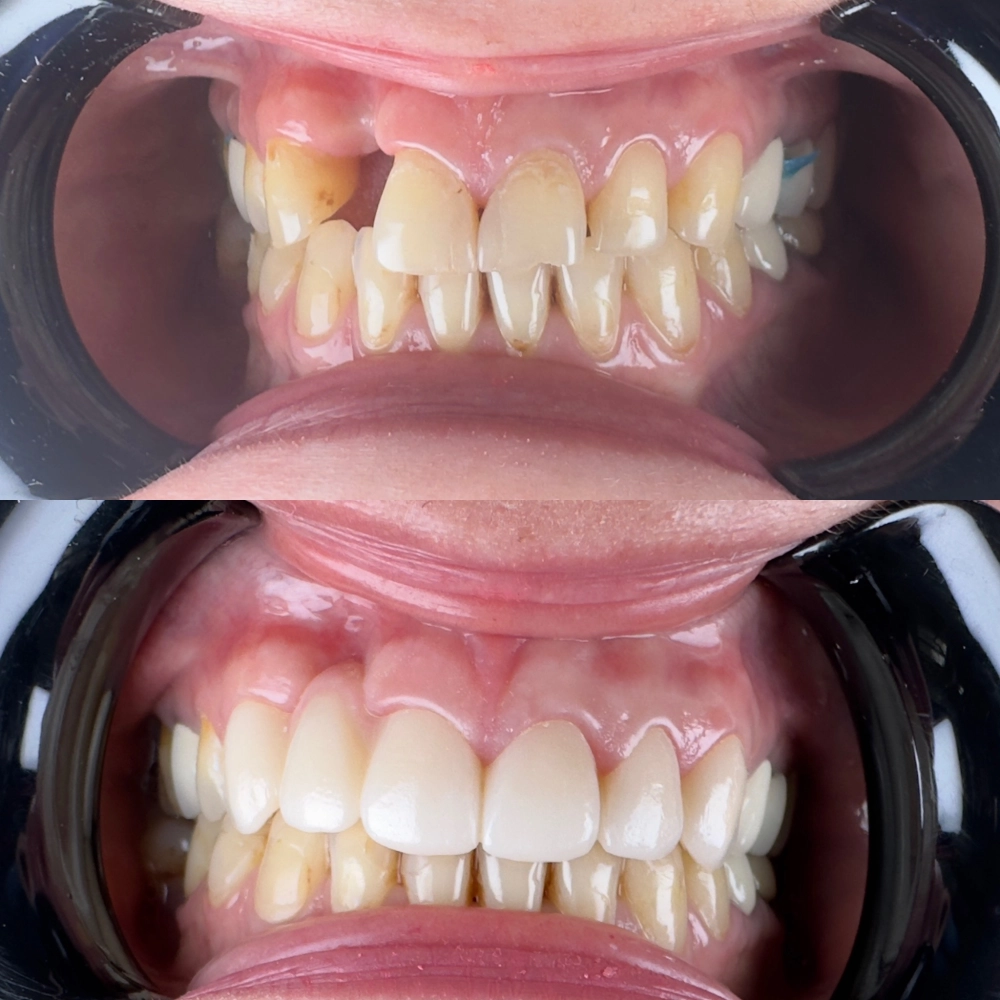

До

После

лечение зубов под микрсокопом